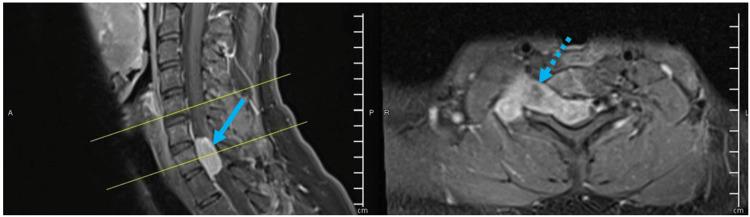

Ewing sarcoma is a rare neoplasm that mostly grows in bones or soft tissues around bones. Most cases of Ewing sarcoma occur in intra-skeletal locations (long bones, pelvis, or ribs) and rarely in extra-skeletal regions such as paravertebral or epidural space, whereas a primary intradural extramedullary Ewing sarcoma (IEES) is extremely rare. Fifty cases of primary IEES including our case were identified in the literature, so far, of which two-thirds are in the lumbosacral region, while only 12 reports described a cervical location of the tumor. Herein, we are presenting a case of C7-T1 primary IEES for a 24-year-old male, followed by a review of updated literature about the primary IEES in the cervical spine.

尤因肉瘤是一种罕见的肿瘤,主要生长于骨骼或骨骼周围的软组织。大多数尤因肉瘤病例发生于骨骼内部(长骨、骨盆或肋骨),很少发生于椎旁或硬膜外间隙等骨骼外区域,而原发性硬脊膜内髓外尤因肉瘤(IEES)极为罕见。迄今为止,文献中已报道了包括我们的病例在内的50例原发性IEES病例,其中三分之二位于腰骶部,而仅有12篇报道描述了肿瘤位于颈椎。在此,我们报告一例24岁男性C7-T1原发性IEES病例,并对颈椎原发性IEES的最新文献进行综述。